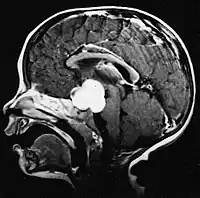

Denne tumor er typisk for den posteriore fossa, hvor den er lokaliseret i begge hjernehalvdele eller i cerebellar vermis. Fordi det er invasivt og hurtigt voksende, spredes det normalt til andre dele af centralnervesystemet (CNS) via CSF og kan infiltrere gulvet i den nærliggende fjerde ventrikel og meninges. Mere sjældent kan yderligere CNS-metastaser forekomme. Når maligniteten opstår, omfatter symptomer tab af balance, ukoordination, dobbeltsyn, dysartri og på grund af involvering af den fjerde ventrikel, hvilket ofte resulterer i obstruktiv hydrocephalus, hovedpine, kvalme og opkastning og ustabil gang.

MR viser normalt en massiv kontrastforstærkende læsion, der involverer lillehjernen. Som nævnt ovenfor har medulloblastom en høj tilbøjelighed til lokalt at infiltrere leptomeninges samt til at sprede sig gennem det subarachnoidale rum, hvilket involverer ventriklerne, cerebral konveksitet og leptomeningeale overflader af rygsøjlen. Det er derfor nødvendigt at bringe hele kraniospinalaksen i resonans.